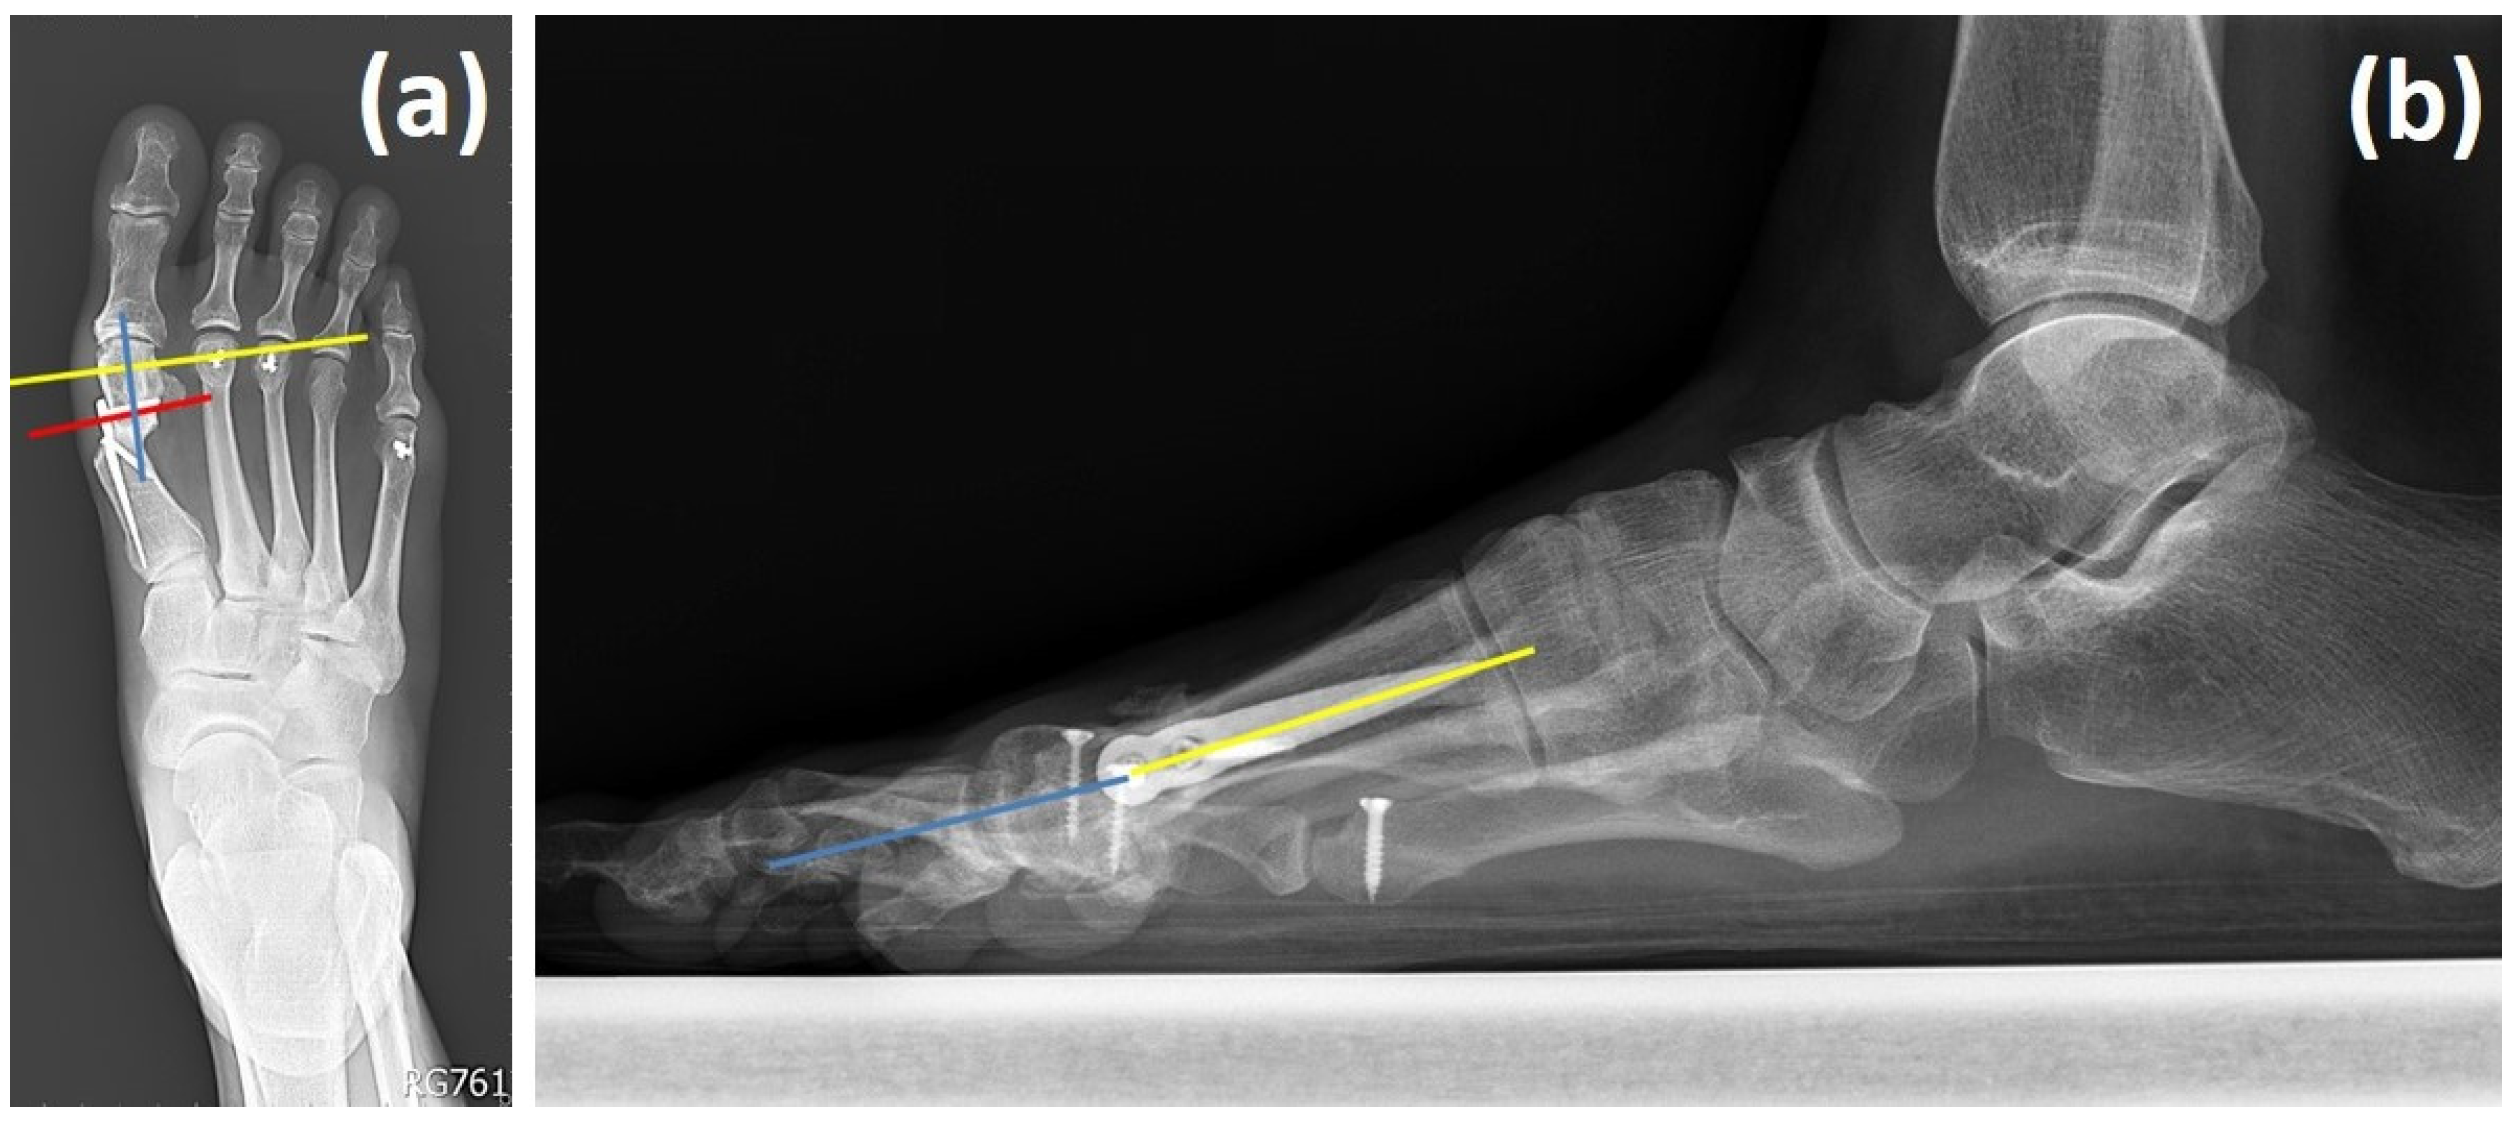

• Distal screw insertion angle: The trajectory of the distal locking screw was carefully adjusted relative to the perpendicular axis of the distal bone fragment to minimize the risk of sagittal plane rotation (Figure 2a). A slight angulation, rather than a strictly perpendicular orientation, was used to improve rotational stability.

• Lateral angulation monitoring: Intraoperative lateral radiographs were examined to ensure proper alignment between the distal metatarsal head and the proximal shaft, allowing for the detection and correction of any angular deformity (Figure 2b).

Figure 2. Two angles to be noted when using the Spear plate. (a) Anteroposterior view of the distal screw insertion angle between the distal screw on the plate (red line) and the line perpendicular to the axis of the distal fragment (yellow line); the axis of the distal fragment (blue line). (b) Lateral view of the lateral angulation angle between the axis of the metatarsal head (blue line) and the axis of the proximal metatarsal shaft (yellow line).